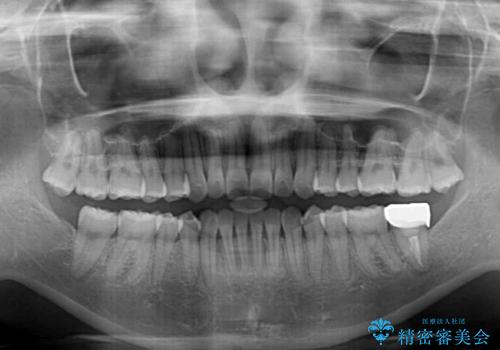

- 矯正治療の後戻りを気にして来院された患者様です。

後戻りは軽微でしたが、舌突出癖が認められ、初診時には上下前歯に舌がはまるスペースができていました。

舌突出癖の改善を行いながら、インビザライン・ライトにより矯正治療を行うこととしました。

舌突出癖の改善により上下前歯が接触するようになり、前歯でものを咬みきる必要のある食事がスムーズに行えるようになりました。